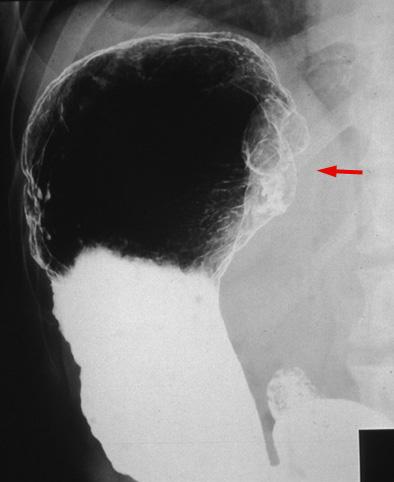

질환(병리주체)의 분류 악성 상피성종양/기타

부위(장기별) 위(부위)/분문

검사방법 X-P

종양의 육안분류 1형(종괴형)/

종양의 최대경(밀리미터) 40이상

종양의 심달도 s(a)